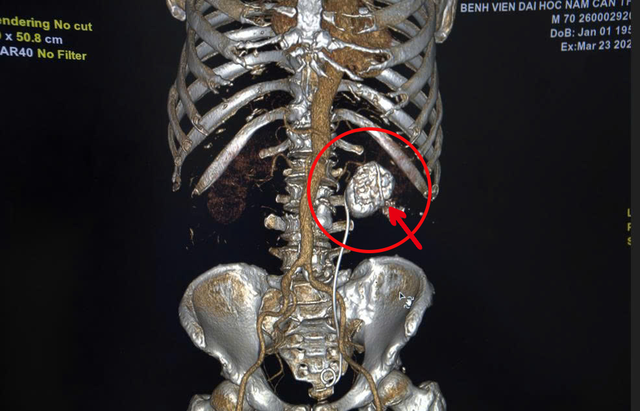

Viên sỏi san hô và ống sonde JJ của bệnh nhân qua hình ảnh chụp MRI

Theo đó, bệnh nhân Sin Nan (69 tuổi, người Campuchia) nhập viện tại Bệnh viện Đại học Nam Cần Thơ sau khi người nhà tìm hiểu thông tin qua mạng xã hội, trong tình trạng đau hông lưng kéo dài. Khai thác tiền sử bệnh cho thấy, trước đó ông Sin Nan đã từng được tán sỏi thận qua da tại cơ sở y tế ở nước ngoài nhưng không thành công, sỏi vẫn tồn tại và tiếp tục tiến triển. Ông Sin Nan còn mang ống sonde JJ niệu quản đã đặt từ trước, sinh hiệu chưa ổn định.

Bên cạnh đó, bệnh nhân Sin Nan có dấu hiệu nhiễm khuẩn đường tiết niệu, gia tăng nguy cơ suy giảm chức năng thận và có tiền sử bệnh lý nền đái tháo đường, tăng huyết áp, làm phức tạp thêm quá trình phẫu thuật. Sau hội chẩn chuyên khoa, PGS.TS.BS. Đàm Văn Cương - Giám đốc Bệnh viện Đại học Nam Cần Thơ cùng ê-kíp các bác sĩ bệnh viện đã tiến hành phẫu thuật cho bệnh nhân Sin Nan, quá trình phẫu thuật diễn ra rất thuận lợi, viên sỏi san hô được lấy trọn với kích thước 5,64mm x 5,80mm, và có trọng lượng nặng 83,848 gram.

Viên sỏi san hô được lấy trọn với kích thước 5,64mm x 5,80mm, và có trọng lượng nặng 83,848 gram